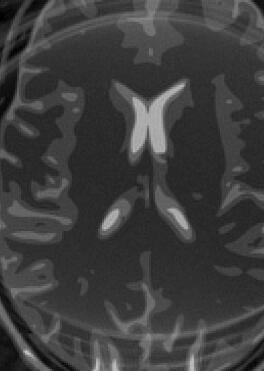

The simulation employs a realistic analytical MRI brain phantom [50], of dimensions , i.e., .

Fig. 14 exhibits the reconstruction results with the spiral trajectory with for . The reconstructed images are displayed alongside profile plots of row . The same is also presented in Figures 13 for .